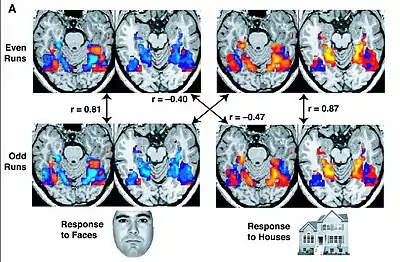

- Tokyo Institute of Technology researchers make a breakthrough in teaching a computer to understand human brain function. The scientists used fMRI datasets to train a computer to predict the semantic category of an image originally viewed by five different people.[534][535]